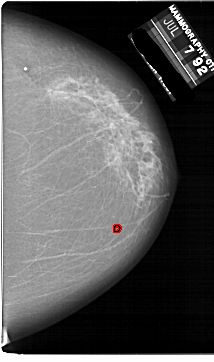

A_1861_1.RIGHT_MLO

RIGHT_MLO LINES 6871 PIXELS_PER_LINE 4426 BITS_PER_PIXEL 12 RESOLUTION 43.5 OVERLAY

FILE: A_1861_1.RIGHT_MLO.OVERLAY

TOTAL_ABNORMALITIES 1

ABNORMALITY 1

LESION_TYPE CALCIFICATION TYPE PLEOMORPHIC DISTRIBUTION CLUSTERED

ASSESSMENT 4

SUBTLETY 2

PATHOLOGY BENIGN

TOTAL_OUTLINES 1

BOUNDARY